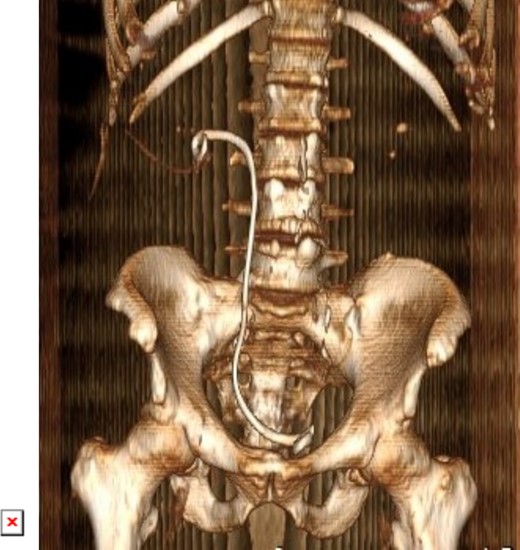

On physical examination, he had normal vital signs, no fever, and exhibited mild tenderness in the suprapubic area and right costovertebral angle. The results of the laboratory tests were normal, and the serum creatinine level was 0.8 mg/dl. Urine culture was negative for bacteria. Preoperative abdominal and pelvic ultrasound revealed two right renal stones, one measuring 4 cm in the upper pole and 2 cm in the lower pole with mild hydronephrosis, along with a large bladder stone measuring 6 cm, and a shadow of a double J stent. A computed tomography (CT) scan confirmed the presence of a 4 cm upper pole renal stone, a 1.8 cm lower pole renal stone, significant proximal pigtail calcification with mild hydronephrosis (Fig. 1A and B), and a 6 cm bladder stone deeply embedded in the distal pigtail (Fig. 2A and B). Additionally, small intrarenal stones were observed on the left side, along with a proximal ureteric stone measuring 8 mm by 9 mm with mild hydronephrosis.

Non-contrast CT scan showed intra-renal stone with significant proximal pigtail calcification and mild degree of hydronephrosis.

3D constructed image of postoperative low dose non-contrast CT scan showing stone clearance and newly inserted DJ stent in-situ.